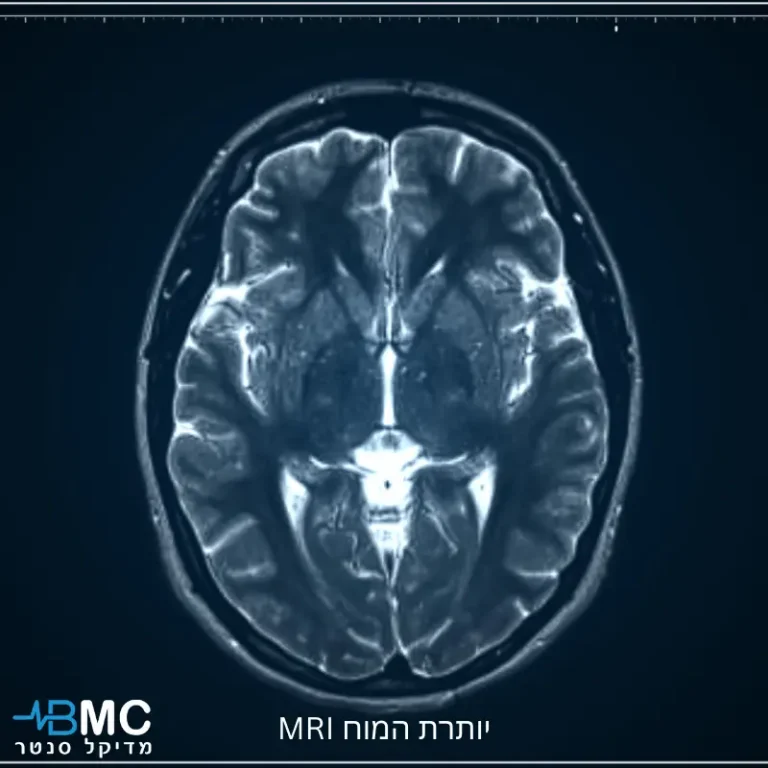

הדמיית תהודה מגנטית (MRI) של המוח היא אחד הכלים החשובים ביותר לאבחון של מחלות נוירולוגיות.

בדיקת MRI (דימות תהודה מגנטית) נחשבת לאחת מטכנולוגיות ההדמיה המתקדמות והרגישות ביותר הקיימות ברפואה המודרנית.